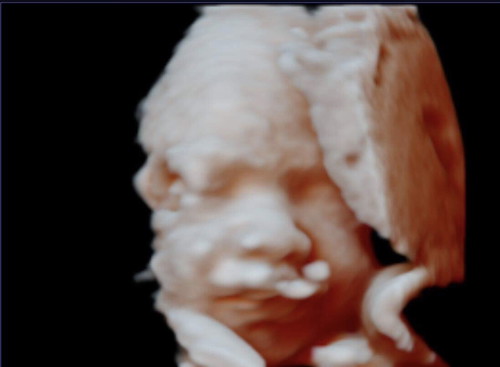

Scan 5D/HD Live

Salam Ibu2 semua Saya cuma nak bg cadangan siapa yg dduk area kemaman Terengganu Boleh buat Scan 5D/HD Live cume Rm89 shj siap dapat CD, gambar baby 3keping dan jga boleh tngok Baby Lebih kurang 1 jam..Dokter sgt2 Peramah..Dokter akn usha utk dptkn Gambar yg terbaik utk Ibu2..kt bawah ni ank sy yg bakal lahir in sha Allah 27 Aug ni..Dokter akn mulakan dr scan details 2d jd dpt la tngok dlman baby jga..Doakan sy dan baby Selamat ye masa saya melahirkan nnt..Terima kasih ??? Nama Klinik : Klinik Ibnu Sina